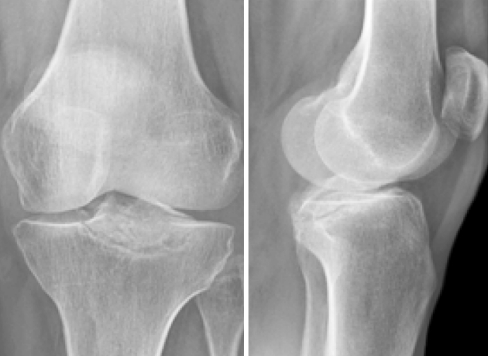

Standard lateral and posterior-anterior radiographs revealed an evident pseudo-arthrosis with a radiolucent and sclerotic line under the posterior tibial eminence. The avulsed fragment measured 32 mm × 24 mm × 12 mm (Fig. 1).

Fig. 1.

Standard radiographs showing an evident pseudo-arthrosis of the posterior tibial eminence